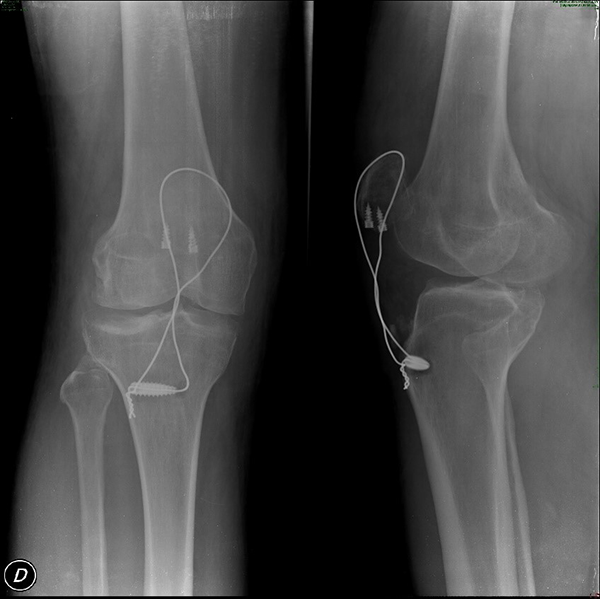

Se realizaron controles radiográficos y de la herida semanalmente. Se indicó movilización activa sin resistencia a la sexta semana y posteriormente rehabilitación gradual con fisioterapia. Se obtuvieron excelentes resultados en cuanto a la capacidad funcional y reincorporación a la actividad laboral (fig. 7).

Figura 7: Radiografía de control en postquirúrgico inmediato.